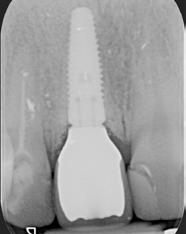

kép). A bemutatott esetben Nobel Replace CC 4,3x13mm implantátumot helyeztünk be, amely a bukkális oldalon direkt kontaktusba került a megmaradt foggyökérdarabbal (7. kép). Az alveolus oldalfalai és a körszimmetrikius implantátum közötti hézag kitöltésére bovin eredetű xenograftot (Creos S xenogain) használtunk (8. kép). A hasonló

A behelyeztt implantátum primer stabilitását megfelelőnek ítéltük (kb. 40 Ncm) az azonnali terheléshez (9. kép). Az extrakciót megelőző szituációs lenyomat alapján gyári, titán, ideiglenes abutment felhasználásával, a szék mellett készített, csavaros rögzítésű, azonnali akrilát ideiglenes koronával láttuk el, melyet 20 Ncm nyomatékkal rögzítettünk (10. kép). Az azonnali terhelés szabályainak megfelelően, az ideiglenes korona nem volt kontaktusban a szomszédos és az antagonista fogakkal.

11. kép: A 6 hónapos kontroll felvétele.

12. kép: A 6 hónapos intraorális kontrollröntgen felvétele.